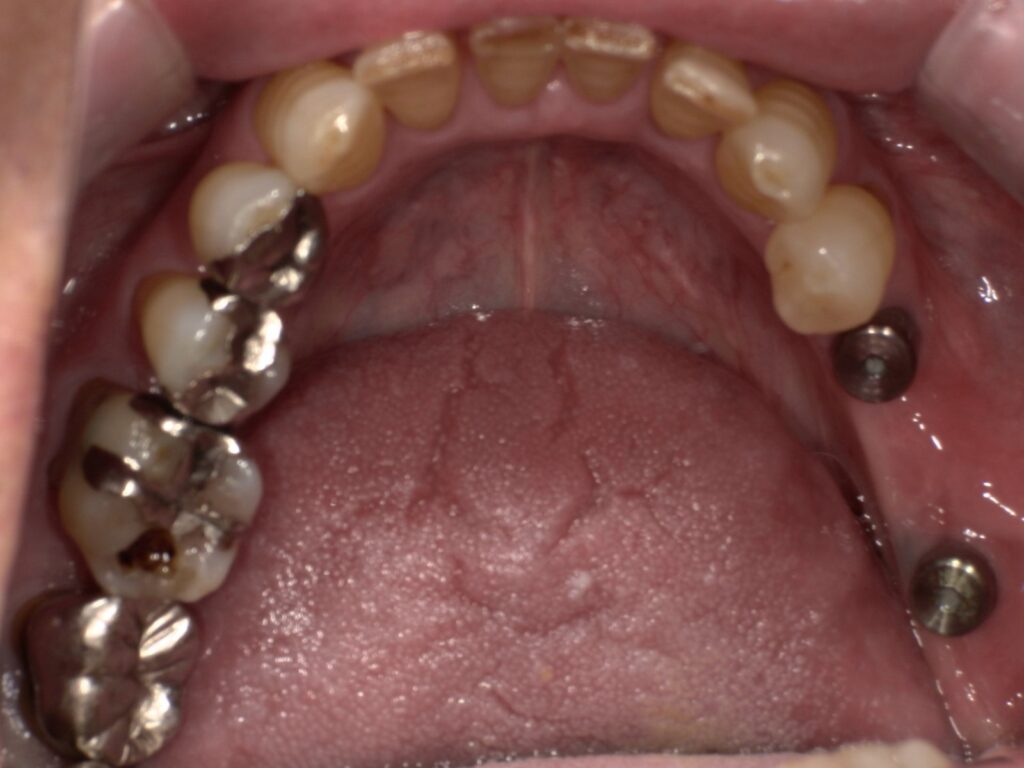

上顎の6番7番にインプラントを埋入した2次オペ後の写真です。

今回は患者様のご希望により、上部構造は銀歯で作成いたしました。

上顎の上部構造セット後の写真です。

こちらも患者様のご希望により、上部構造は銀歯で作成いたしました。